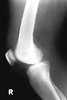

Calcium pyrophosphate dihydrate crystal deposition disease

Calcium pyrophosphate dihydrate (CPPD) crystal deposition disease, also known as pseudogout and pyrophosphate arthropathy, is a rheumatologic disease which is thought to be secondary to abnormal accumulation of calcium pyrophosphate dihydrate crystals within joint soft tissues. The knee joint is most commonly affected. [Source: Wikipedia ]